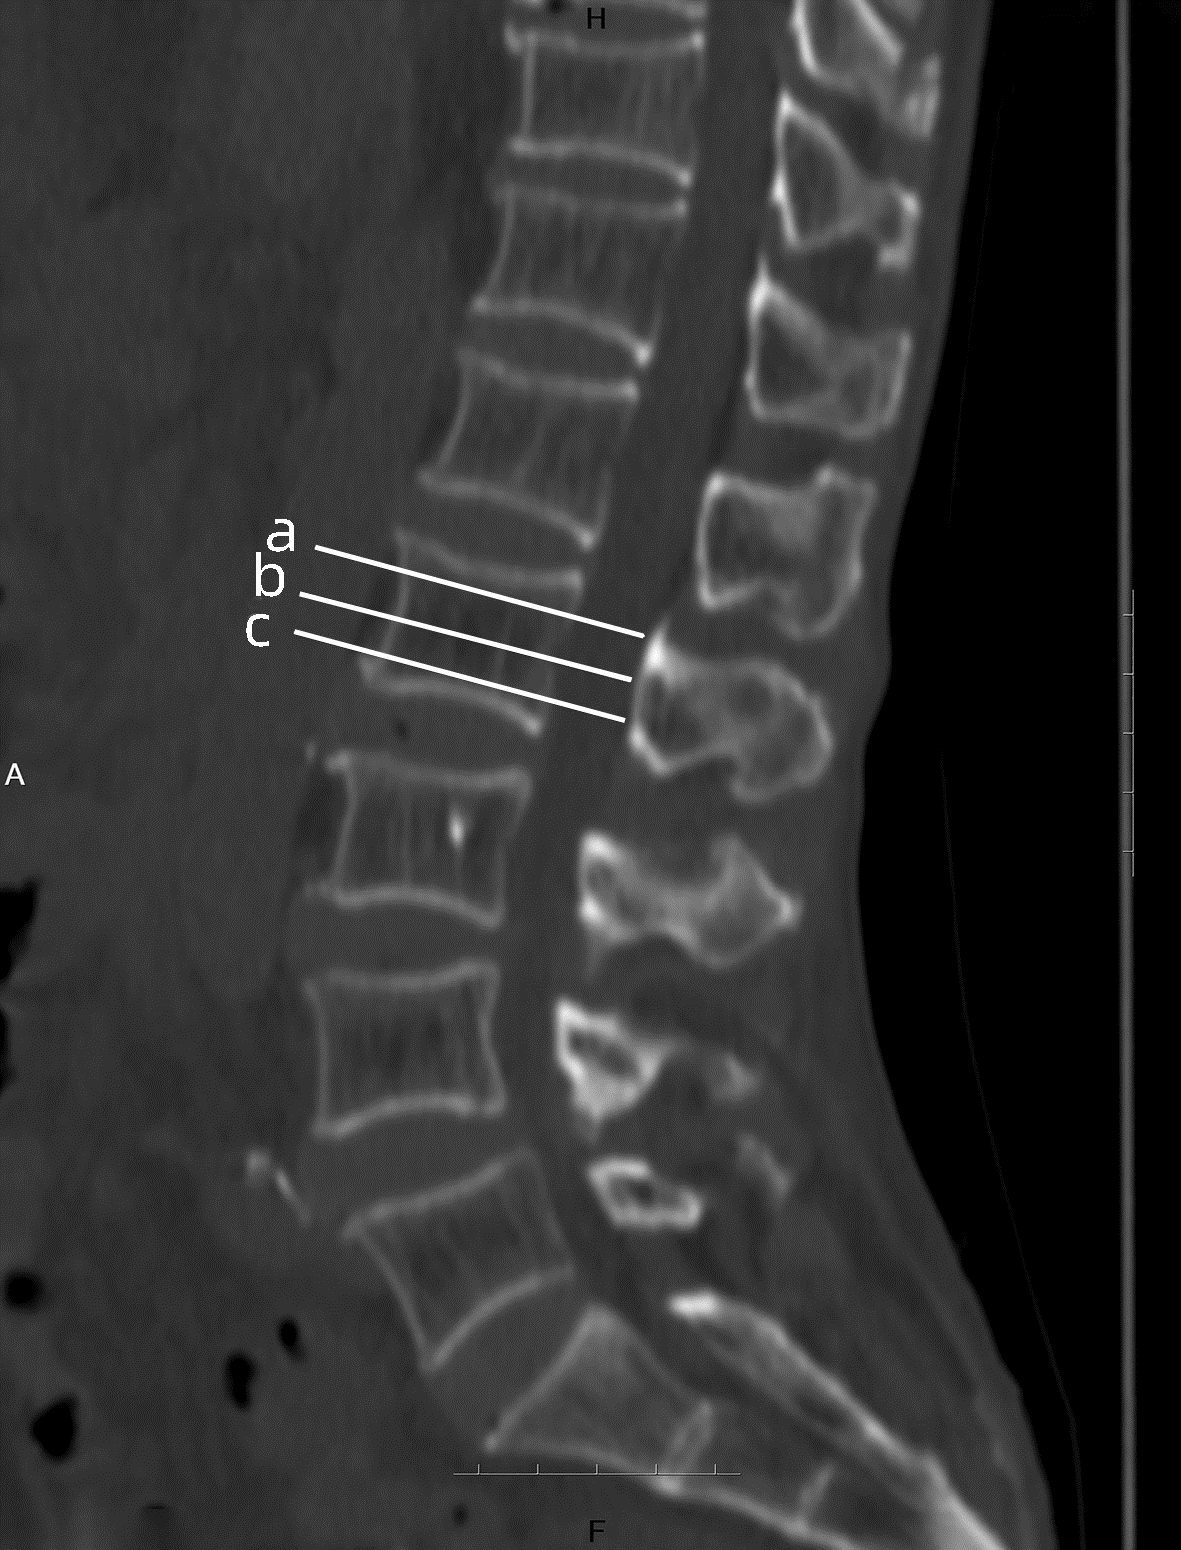

慢性乙型肝炎患者骨量减少/骨质疏松的危险因素及CT值的诊断价值

张静怡, 唐映梅, 李嘉琦, 王倩, 张宸瑞

2022, 38(5): 1041-1047. DOI: 10.3969/j.issn.1001-5256.2022.05.013

摘要(1220) HTML (508) PDF (2526KB)(83)

摘要:

目的  评价在慢性乙型肝炎患者腹部CT中通过测量胸、腰椎CT值,诊断骨量减少/骨质疏松的诊断价值。分析慢性乙型肝炎患者发生骨量减少/骨质疏松的危险因素。  方法  回顾性纳入2019年1月—2020年12月在昆明医科大学第二附属医院就诊的慢性乙型肝炎患者112例,所有患者均完善了腹部CT检查,部分患者完善了双能X线骨密度测定(DXA)。测量T12椎体至L3椎体的CT值,分析每一椎体CT值与DXA检查基于L1~L4椎体测得的T-score值相比诊断骨量减少/骨质疏松的诊断价值。以椎体CT值为诊断标准,将纳入的慢性乙型肝炎患者分为骨量减少/骨质疏松组(n=55)与骨量正常组(n=57),对比两组患者临床特征、生化指标,分析慢性乙型肝炎患者发生骨量减少/骨质疏松的危险因素。符合正态分布的计量资料两组间比较采用t检验;非正态分布的计量资料两组间比较采用Mann-Whitney U检验。计数资料组间比较采用χ2检验、Fisher确切检验、Bonferroni校正检验。相关性采用Pearson相关分析。多因素分析采用二元logistic回归分析。根据受试者工作特征曲线(ROC曲线)评估T12~L3椎体CT值诊断慢性乙型肝炎患者合并骨量减少/骨质疏松的诊断价值。一致性检验采用Kappa检验。  结果  分析46例在同次住院中完善了腹部CT和DXA检查患者的T12~L3椎体CT值,均分别与DXA检查结果中基于L1~L4椎体计算的T-score值有显著正相关性(rT12=0.694,rL1=0.661,rL2=0.781,rL3=0.685,P值均<0.001);经ROC曲线分析,L2椎体CT值ROC曲线下面积最大(0.863),诊断骨量减少/骨质疏松具有较好准确性,与DXA检查结果具有较好一致性(K=0.648,P<0.001)。分析112例慢性乙型肝炎患者临床特征、生化指标,提示高龄(比值比为1.108,95%CI:1.026~1.196,P=0.009)、合并肌少症(比值比为2.788,95%CI:1.009~7.707,P=0.048) 是骨量减少/骨质疏松发生的危险因素。  结论  慢性乙型肝炎患者常需定期复查腹部CT评估肝脏疾病进展情况,通过测量患者腹部CT图像中L2椎体CT值、L3椎体层面骨骼肌面积筛查是否存在骨量减少/骨质疏松、肌少症,及时干预,提高患者的预后、生活质量,具有较高临床意义。